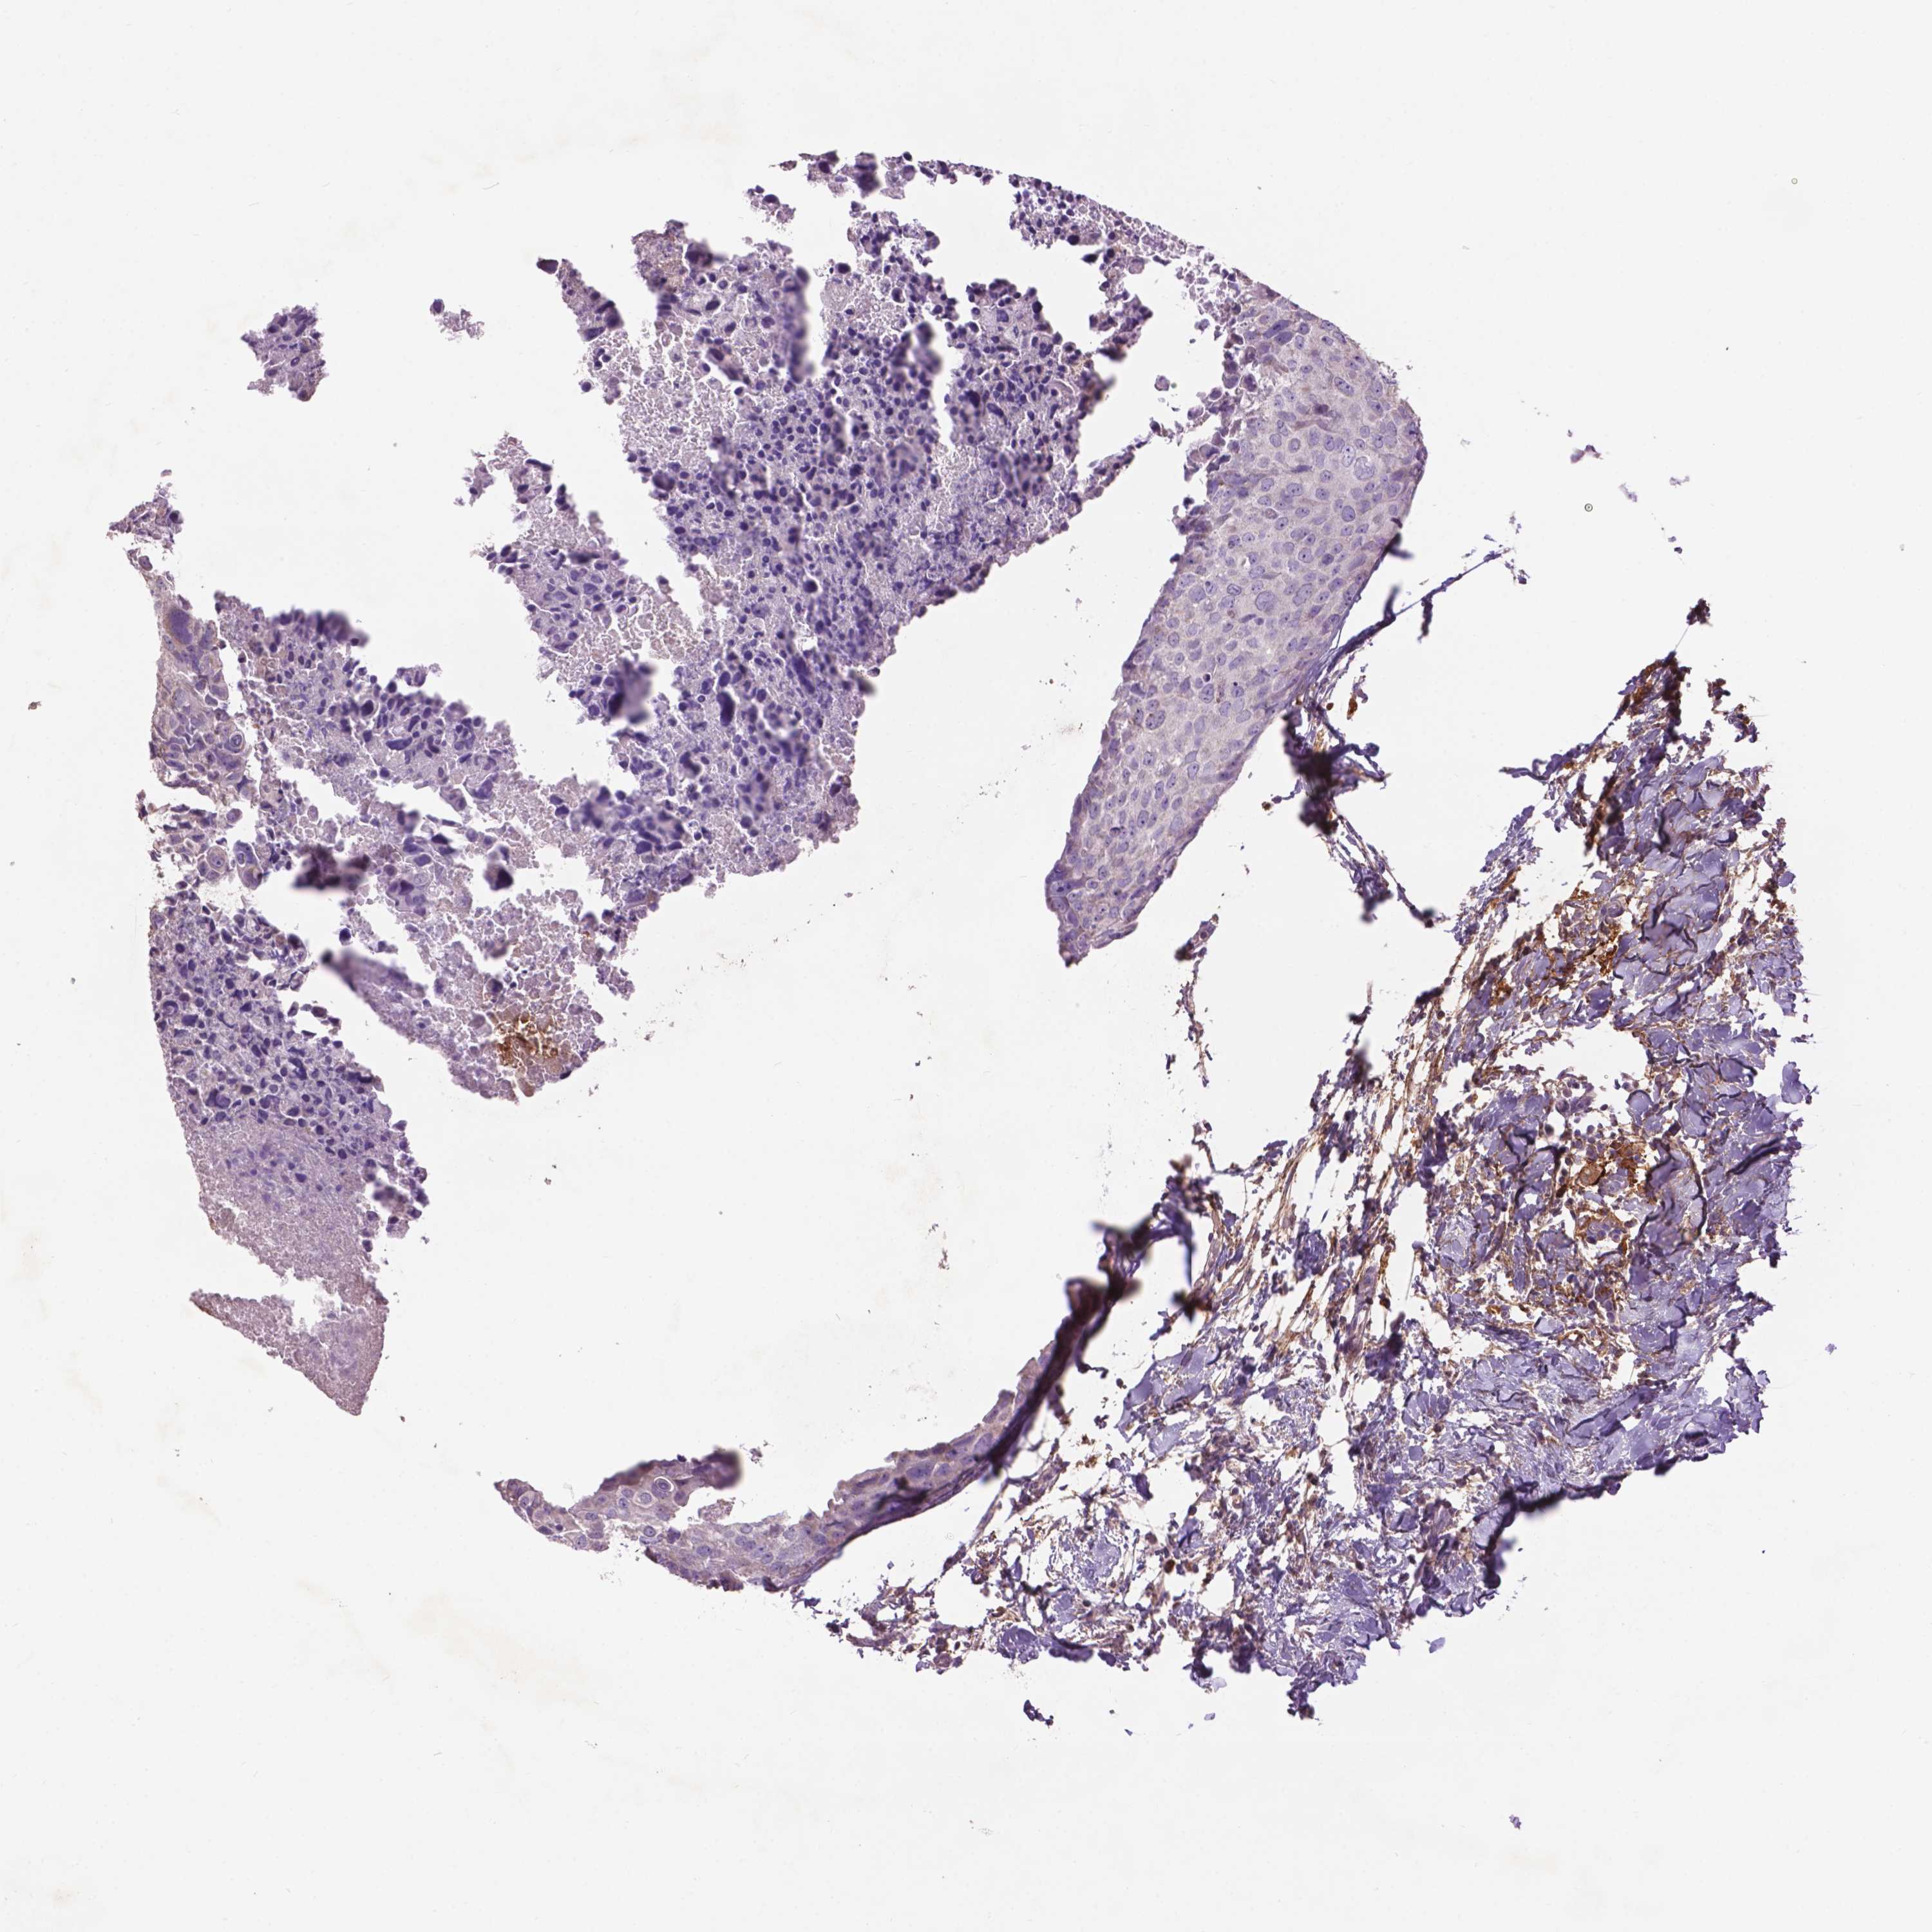

BRCA TCGA BRCA VALIDATION PROTEIN EXPRESSION

ANTIBODIES

AND

VALIDATION